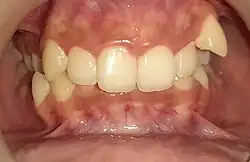

Overbite is the extent of vertical (superior-inferior) overlap of the maxillary central incisors over the mandibular central incisors,[1] measured relative to the incisal ridges.[2]

The term overbite does not refer to a specific condition, nor is it a form of malocclusion. Rather an absent or excess overbite would be a malocclusion. Normal overbite is not measured in exact terms, but as a proportion (approximately 30–50% of the height of the mandibular incisors) and is commonly expressed as a percentage.

Overbite is often confused with overjet, which is the distance between the maxillary anterior teeth and the mandibular anterior teeth in the anterior-posterior axis.

"Overbite" may also be used commonly to refer to Class II malocclusion or retrognathia, though this usage can be considered incorrect. This is where the mesiobuccal cusp of the maxillary first molar is situated anterior to the buccal groove of the mandibular first molar; in other words, the mandible (lower jaw) appears too far behind the maxilla. A person presenting with Class II malocclusion may exhibit excessive overbite as well, or may have the opposite problem, which is referred to as openbite (or apertognathia). In the case of apertognathia, and the teeth do not overlap enough or at all—the upper teeth protrude past the lower teeth. An open bite is a condition where the upper and lower teeth do not meet or bite in the correct position. Unlike an overbite or underbite, there is no overlapping of teeth, giving an impression of the teeth appearing "open". A mild case of open bite can be treated with Invisalign, a popular orthodontic treatment using clear aligners. Orthodontists often recommend Invisalign to correct mild forms of open bites. However, severe open bite cases may require alternative treatments, such as surgery or other orthodontic methods.